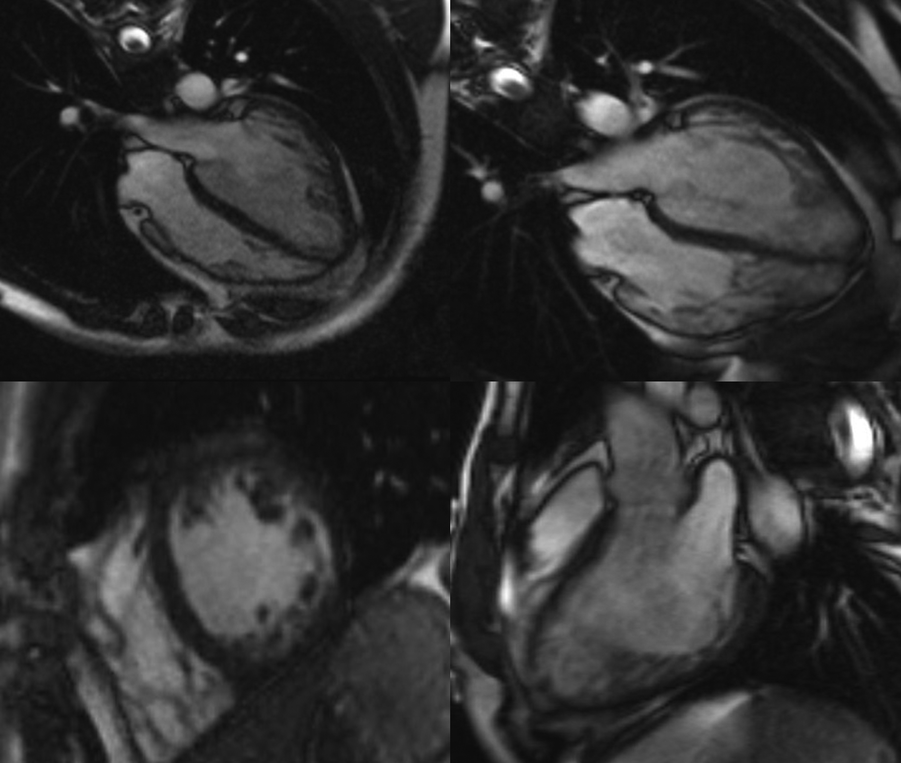

On admission, echocardiography and cardiac magnetic resonance imaging were performed to determine the presence of structural deterioration that could be attributed to the observed dysrhythmic changes. Recently performed coronary angiography with no evidence of stenosis or atherosclerosis excluded the ischemic etiology of NSVT. Transthoracic echocardiography using Vivid E95 Cardiac Ultrasound (GE Healthcare, Chicago, IL, USA) revealed a degenerative aortic and mitral valve with normal overture and kinetics maintained, respectively. Myocardial thickness was normal, but global hypokinesia was described while the interventricular septum and the inferoposterior wall of the myocardium showed decreased contractility. The global ejection fraction of the left ventricle was estimated to be 45%. Additionally, transmitral diastolic flow with a biphasic pattern of abnormal LV relaxation (I/IV grade LV diastolic dysfunction) was noted. Cine cardiac magnetic resonance (CMR) steady-state free precession sequences showed a dilated left ventricle with septum hypo-dyskinesia and an ejection fraction of 48%, as well as excessive trabeculation in segments 13, 15, and 16, and a part of segments 7 and 10 with a non-compact to compact myocardium (NC/C) ratio higher than 2.3 in end-diastole (Figure 2). In the late gadolinium enhancement (LGE) sequences with phase-sensitive inversion recovery (PSIR), there were an LGE midwall striae in the basal and midseptums (Supplementary Figure S1).

Figure 2

Cine cardiac magnetic resonance images of left ventricular cardiomyopathy with excessive trabeculation. Representative images of cine cardiac magnetic resonance imaging (CMR) steady-state free precession (SSFP) sequences at the time of diagnosis of cardiomyopathy with excessive trabeculation (left panel) and the onset of amiodarone-induced thyroiditis (right panel). The first row of images represents the four-chamber view through the horizontal long axis, whereas the second row consists of the short-axis pre-contrast scan (left panel) and vertical long-axis scan (right panel). Magnetic Resonance Imaging Scanner Siemens Magnetom® Avanto 1.5T (Siemens Medical Solutions, Inc., Hoffman Estates, IL, USA) was used to acquire CMR scans.

Pathological non-compaction, distinguished by an NC/C ratio higher than 2.3 in diastole, was the main morphological criterion used for the validation of LVNC two years before the current admission (17). The left ventricular ejection fraction was mildly reduced (LVEF 46%), but the mid-ventricular imbibition of the interventricular septum and its insertion in segment 9 in late post-contrast sequences was minimal then (Supplementary Figure S1). Based on new terminology (16), the patient most likely has dilated cardiomyopathy with excessive trabeculation of the myocardium, according to increased volume of both ventricles and decreased systolic function of the left ventricle with signs of myocardial fibrosis typical for dilated cardiomyopathy (Supplementary Figure S1). Differential diagnosis also included status post myocarditis, but pathognomonic imaging signs of acute myocarditis were not detected at relevant time points (Supplementary Figure S2). The difference in LGE observed between the two CMR imaging time points may suggest disease progression of dilated cardiomyopathy with excessive trabeculation (Supplementary Figure S1) but does not fully explain the observed cECG report.